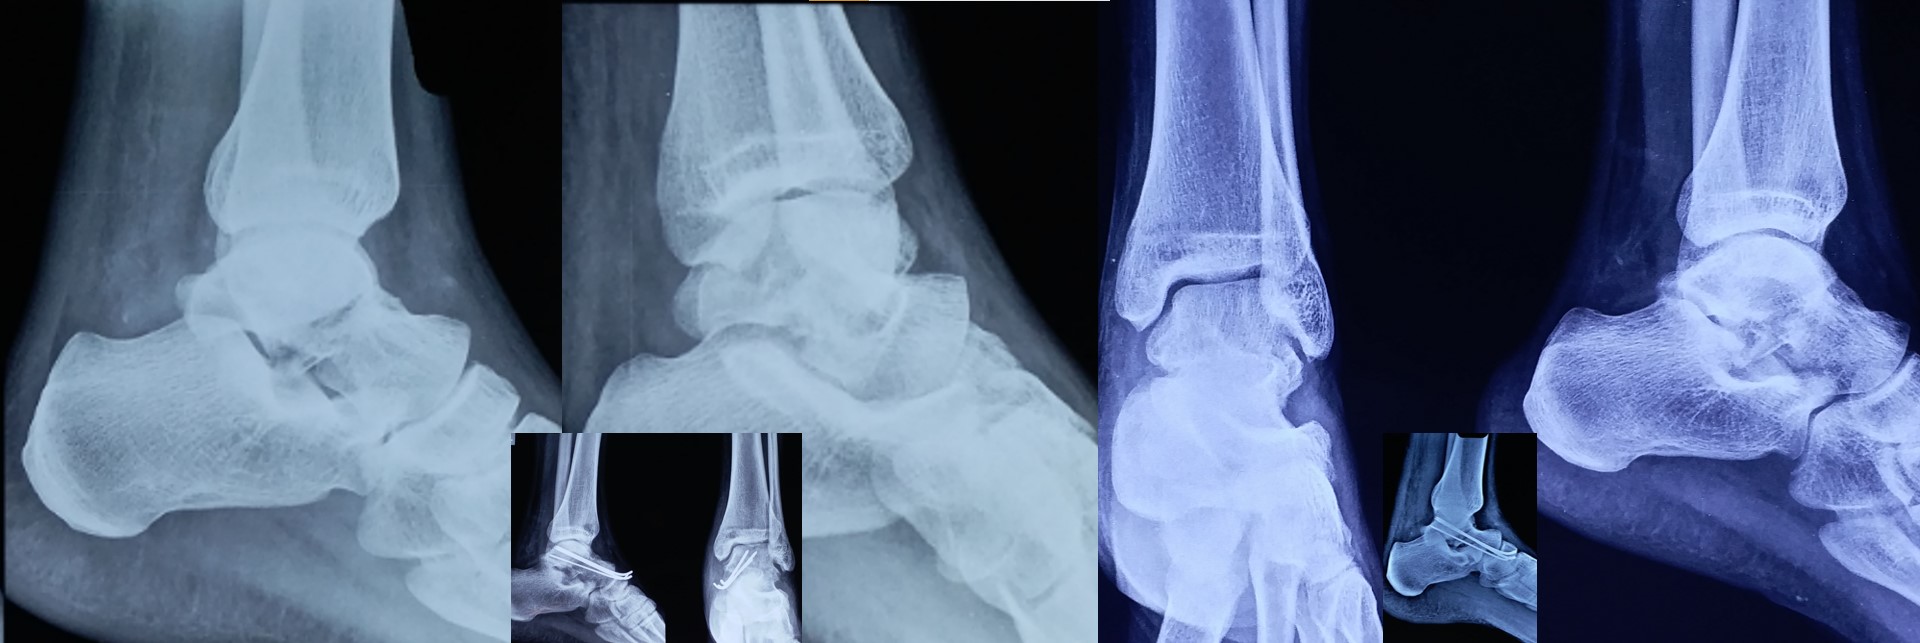

CRPP ( Closed Reduction Percutaneous Pinning )

• No skin incision is required, and fracture heals faster than open surgeries as there is no iatrogenic soft tissue damage or disturbance to the fracture hematoma.

• No implants projecting outside the skin and hence painless adjacent joint movement is possible immediately after CRPP.

• It can be applied to any intraarticular fractures, distal end radius, elbow, ankle and foot.

• It can be applied safely in fractures, where ORIF (Open Reduction Internal Fixation ) cannot be performed or postponed due to impending soft tissue complications.